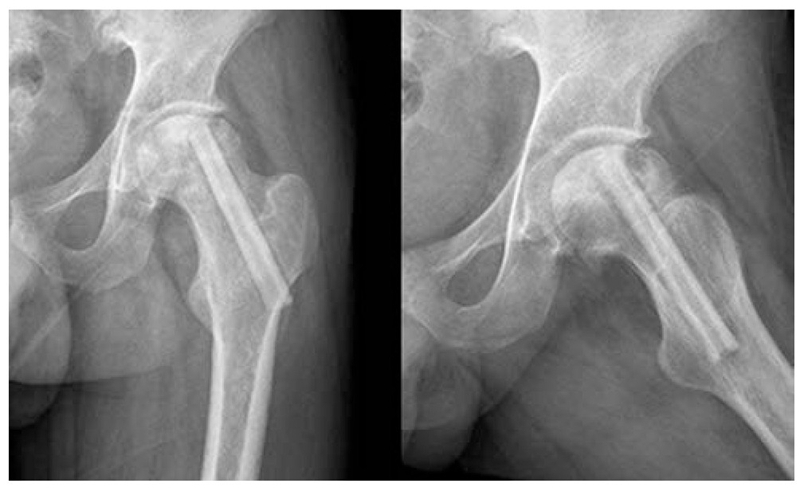

单孔髓芯减压术是使用8~10mm的环钻或空心针,在X线透视下从转子下方骨皮质经股骨颈达到股骨头坏死区域,进而清除坏死骨组织,其临床疗效常取决于分期。

2、细孔径双通道钻孔髓芯减压术

1987年起,浙江省中医院团队设计粗隆下5mm孔径、双通道、股骨头倒V形钻孔加丹参灌注,治疗成人股骨头坏死54例,经过2~8.5年临床观察显示,该方法疗效明显,总优良率达81%,Ⅰ~Ⅱ期优良率达94%。

3、多孔细针(Multiple CD,MCD)髓芯减压术

为了克服单孔髓芯减压术的缺点,科学家们进行了改进,采用细针进行多孔道的髓芯减压,通过以直径为3-4mm的克氏针代替传统钻头,进行多方向多孔道的减压MCD和SCD相比,可到达更多的坏死区域,减压更彻底,手术创伤更小。由于对股骨头、股骨颈处结构影响小,保留孔道之间的支撑结构,因此股骨头塌陷、骨折等并发症发生率也更低。